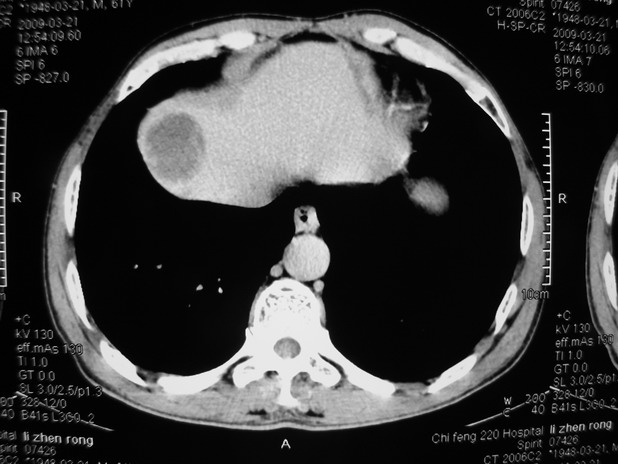

以下是引用余辉在2009-3-21 21:36:00的发言:[br]图像太乱了,建议楼主直接将强化数据按顺序列出来,病灶位置较表浅薄,有肝炎病史,灶内实性成分有显著强化,动脉期约60hu,考虑肝癌可能性大,进一步检查。